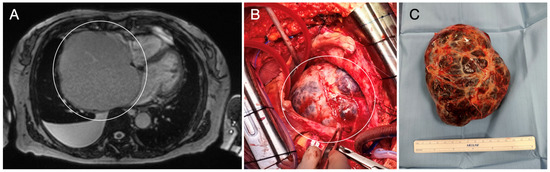

- Chan, E.Y.; Ali, A.; Umana, J.P.; Nguyen, D.T.; Hamilton, D.J.; Graviss, E.A.; Ravi, V.; MacGillivray, T.E.; Reardon, M.J. Management of primary cardiac paraganglioma. J. Thorac. Cardiovasc. Surg. 2022, 164, 158–166.e1. [Google Scholar] [CrossRef] [PubMed]